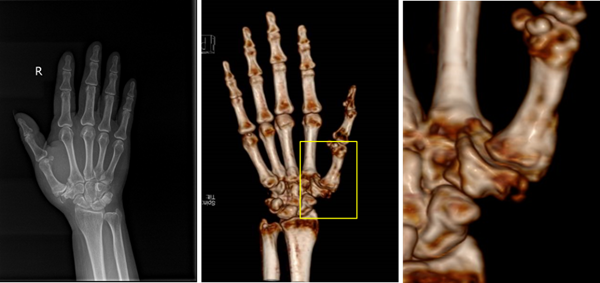

△術(shù)前影像學(xué)檢查提示右側(cè)第一腕掌關(guān)節(jié)炎,腕掌關(guān)節(jié)半脫位

經(jīng)評估檢查,趙德偉團(tuán)隊認(rèn)為該患者關(guān)節(jié)面損毀嚴(yán)重,已經(jīng)進(jìn)展至晚期腕掌關(guān)節(jié)炎階段。采用保守治療,將無法解決關(guān)節(jié)面問題,術(shù)后可能繼續(xù)殘留關(guān)節(jié)疼痛。經(jīng)過與患者充分溝通交流,最終決定采取3D打印多孔鉭金屬人工第一腕掌關(guān)節(jié)置換術(shù)。

趙德偉教授團(tuán)隊經(jīng)過采集患者的CT數(shù)據(jù),量身定制了一套完全匹配于阿姨關(guān)節(jié)角度和尺寸的3D打印多孔鉭金屬人工第一腕掌關(guān)節(jié)假體,將患者受累的腕掌關(guān)節(jié)面替換為人工材料,一次手術(shù)改善患者關(guān)節(jié)炎的問題,減輕患者術(shù)后疼痛,改進(jìn)關(guān)節(jié)功能。